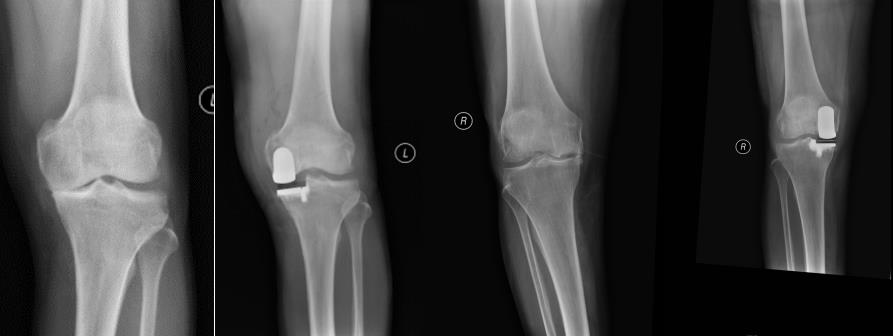

膝关节骨性关节炎,股骨内髁坏死,行微创单髁置换消除疼痛,关节功能恢复正常,患者恢复后自我感觉“未做过手术”。